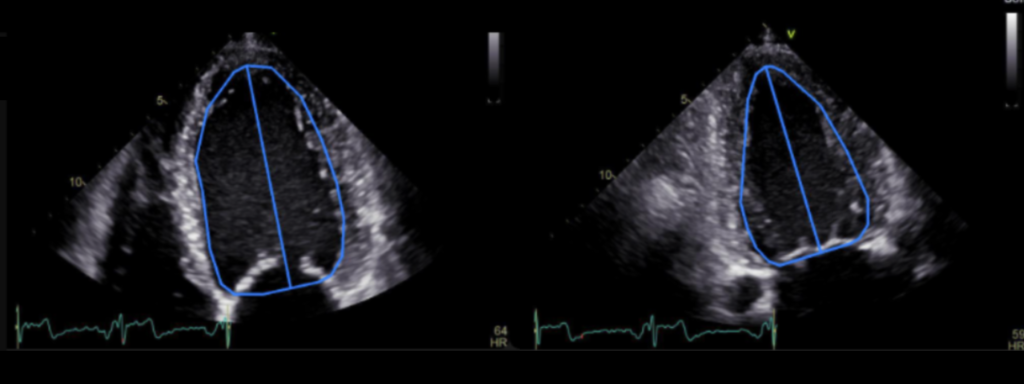

Lithuania, November 26th, 2025 – Ligence announces that its AI-powered echocardiography software, Ligence Heart, has received U.S. Food and Drug Administration (FDA) 510(k) clearance. Ligence Heart, is an AI-powered software that automates measurements and analysis of 2D transthoracic echocardiography (TTE) images and produces a structured report with several key cardiac structural and functional parameters. The clearance enables U.S. healthcare providers to generate reliable and reproducible cardiac measurements, addressing time-consuming tasks in echocardiography analysis.

The number of cardiac diseases each year continues to rise. Manual measurements and reporting consume valuable clinician time, often creating backlogs and adding pressure on already-stretched cardiology teams. Ligence Heart automatically performs key cardiac measurements and generates a clinical report. It is engineered for consistency and operational efficiency with the goal of reducing repetitive manual work and creating a standardised workflow.

With FDA 510(k) clearance, Ligence Heart can now be used in the United States for automated and manual analysis of adult 2D TTE images and reporting. To support the 510(k) submission, Ligence Heart underwent a clinical validation study at an independent U.S. echocardiography core laboratory.